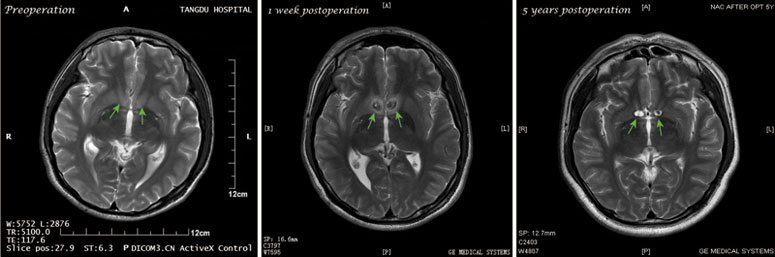

Κινέζοι νευροχειρούργοι προσπαθούν πλέον να καταπολεμήσουν τον εθισμό

στις οπιούχες ουσίες μέσω της καταστροφής μίας περιοχής του εγκεφάλου ο

οποίος ρυθμίζει τα αισθήματα της χαράς.